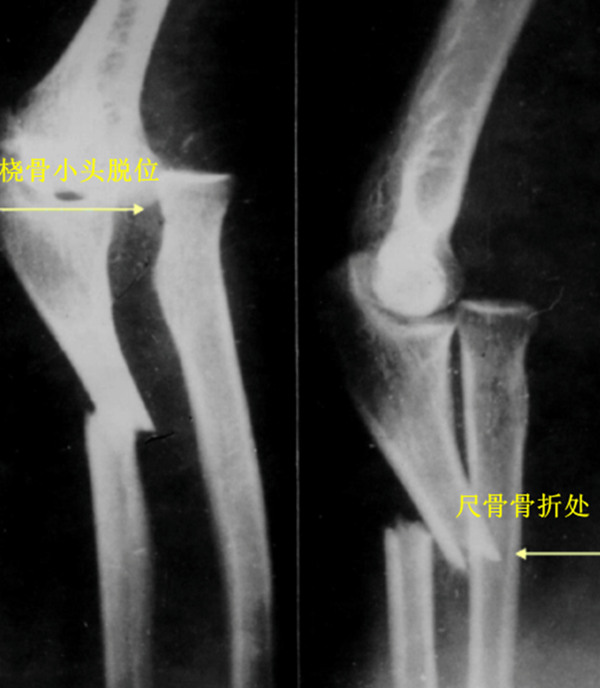

新鲜孟氏骨折的X线片评估内容必须包括标准尺桡骨正侧位片,摄片范围包括腕关节和肘关节。正常情况下,无论肘关节屈伸角度如何,经过桡骨颈和桡骨头中心的线应该通过肱骨小头的中心。